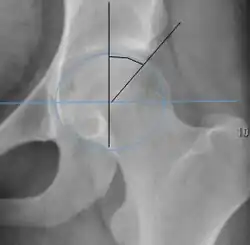

Measurements of impingement on X-ray.[notes 1][20]

Measurement Image Target Normal value

Alpha angle

Measured in 45° Dunn view.

Degree of bulging of the femoral head-neck junction: In normal conditions there is a symmetric concave contour at the junction of the femoral head and neck. Loss of this concavity or bone bulging may lead to cam type impingement. The degree of this deformity can be measured by the alpha angle. Although it can be measured in the cross-lateral view, the 45° Dunn view is considered more sensitive and the frog leg view more specific in determining pathologic values.

• Normal: ≤68° in men, ≤50° in women

• Borderline: 69° to 82° in men, 51° to 56° in women

• Pathological: ≥83° in men and ≥57° in women